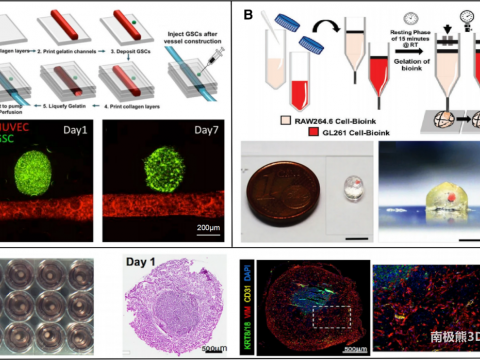

- 浙江大学马梁等:基于生物3D打印的体外肿瘤模型构建

- 美国南卡罗来纳大学Xiao等 | 生物工程女性生殖模型